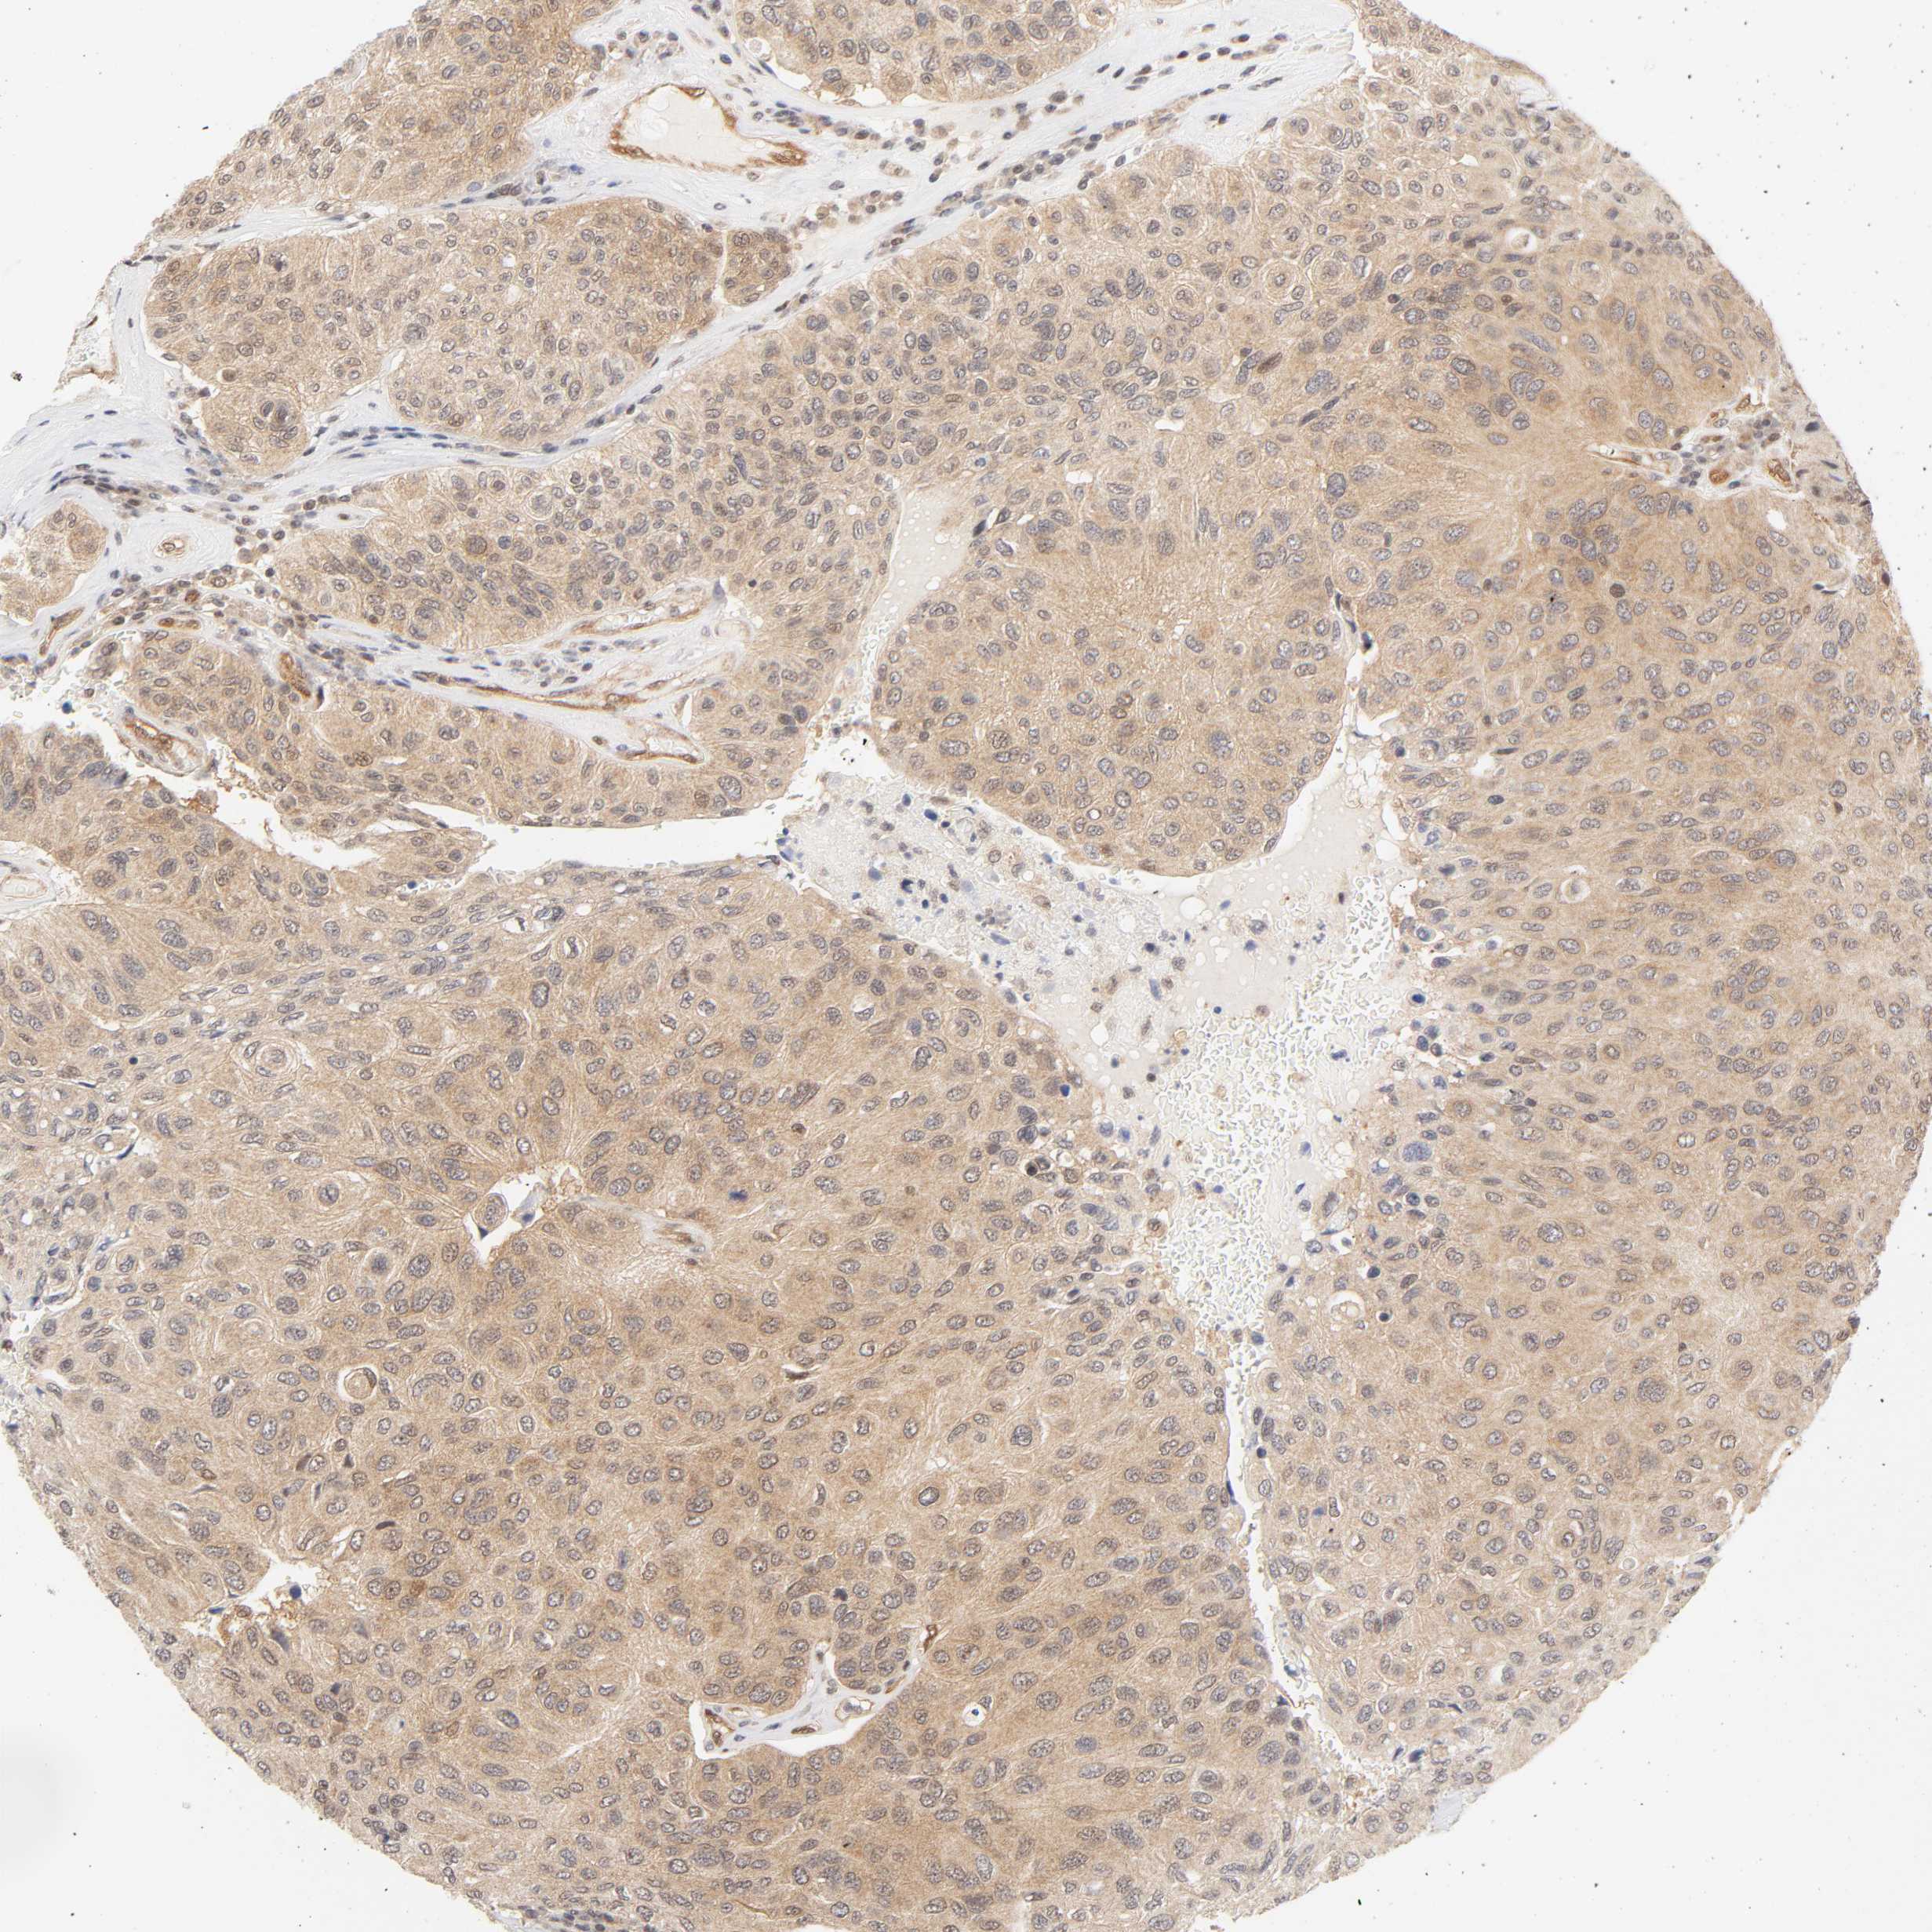

UROTHELIAL CANCER - Protein expressioni

A mouse-over function shows sample information and annotation data. Click on an image to view it in a full screen mode. Samples can be filtered based on level of antibody staining by selecting one or several of the following categories: high, medium, low and not detected. The assay and annotation is described here.

Note that samples used for immunohistochemistry by the Human Protein Atlas do not correspond to samples in the TCGA dataset.

Antibody stainingi

Antibody staining in the annotated cell types in the current human tissue is reported as not detected, low, medium, or high, based on conventional immunohistochemistry profiling in selected tissues. This score is based on the combination of the staining intensity and fraction of stained cells.

Each image is clickable and will lead to virtual microscopy that enables deeper exploration of all samples and also displays staining intensity scores, fraction scores and subcellular localization as well as patient and tissue information for each sample.

Antibody HPA003928

Antibody CAB004214

Staining

High

Medium

Low

Not detected

Intensity

Strong

Moderate

Weak

Negative

Quantity

>75%

75%-25%

<25%

None

Location

Nuclear

Cytoplasmic/membranous

Cytoplasmic/membranous,nuclear

Urothelial carcinoma, High grade

Urothelial carcinoma, Low grade